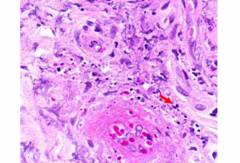

Процессы, происходящие в сосудах при узелковом периартериите:

- развитие аутоиммунного воспаления в сосудистой стенке, в результате которой происходит ее разрушение, разрастание и повышение свертываемости крови;

- перекрытие просвета сосудов, в результате чего нарушается кровоснабжение органов;

- тромбоз сосудов;

- аневризмы (истончение стенки) и разрывы сосудов;

- инфаркты (гибель ткани в результате прекращения кровообращения) во внутренних органах, после которых развивается атрофия и рубцевание, нарушаются функции.

Как выглядит узелковый периартериит на фото?